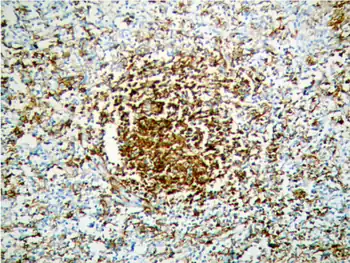

| Morphology of Splenic marginal zone lymphoma | |

Reactive germinal centers in splenic white pulp are replaced by small neoplastic lymphocytes that efface the mantle zone and ultimately blend in with the marginal zone with occasional larger neoplastic cells that resemble blasts.[12][13] The red pulp is always involved, with both nodules of larger neoplastic cells and sheets of the small neoplastic lymphocytes. Other features that may be seen include sinus invasion, epithelial histocytes, and plasmacytic differentiation of neoplastic cells.